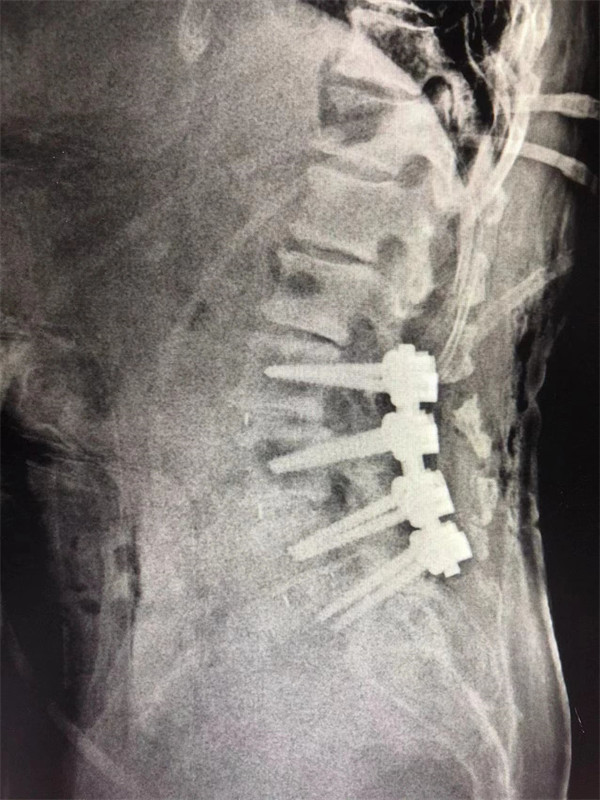

戈才華主任團(tuán)隊(duì)討論病情及手術(shù)風(fēng)險(xiǎn),并與麻醉科醫(yī)生多次討論術(shù)中麻醉風(fēng)險(xiǎn),經(jīng)過(guò)詳盡周密的布置之后,最終給阿婆在全麻下進(jìn)行腰3/4,4/5,腰5/骶1腰椎椎體間融合術(shù)。

手術(shù)后↓